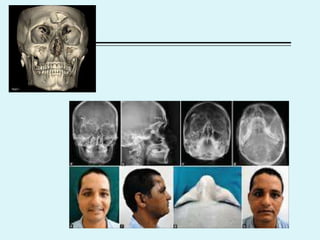

Maxilla #

 3 types

 Lefort

 Clinical features

 Malocclusion of teeth, elongation of midface, mobility of maxilla, csf

rhinorrhoea( II & III)

 Diagnosis

 CT PNS, Water’s , postero-anterior, lateral

 Treatment

 Immediate

 Airway

 Hemorrhage- maxillary artery br

 Fixation (interdental wiring, intermaxillary wiring- arch bars, Open

reduction with intraosseous wiring & wire slings)